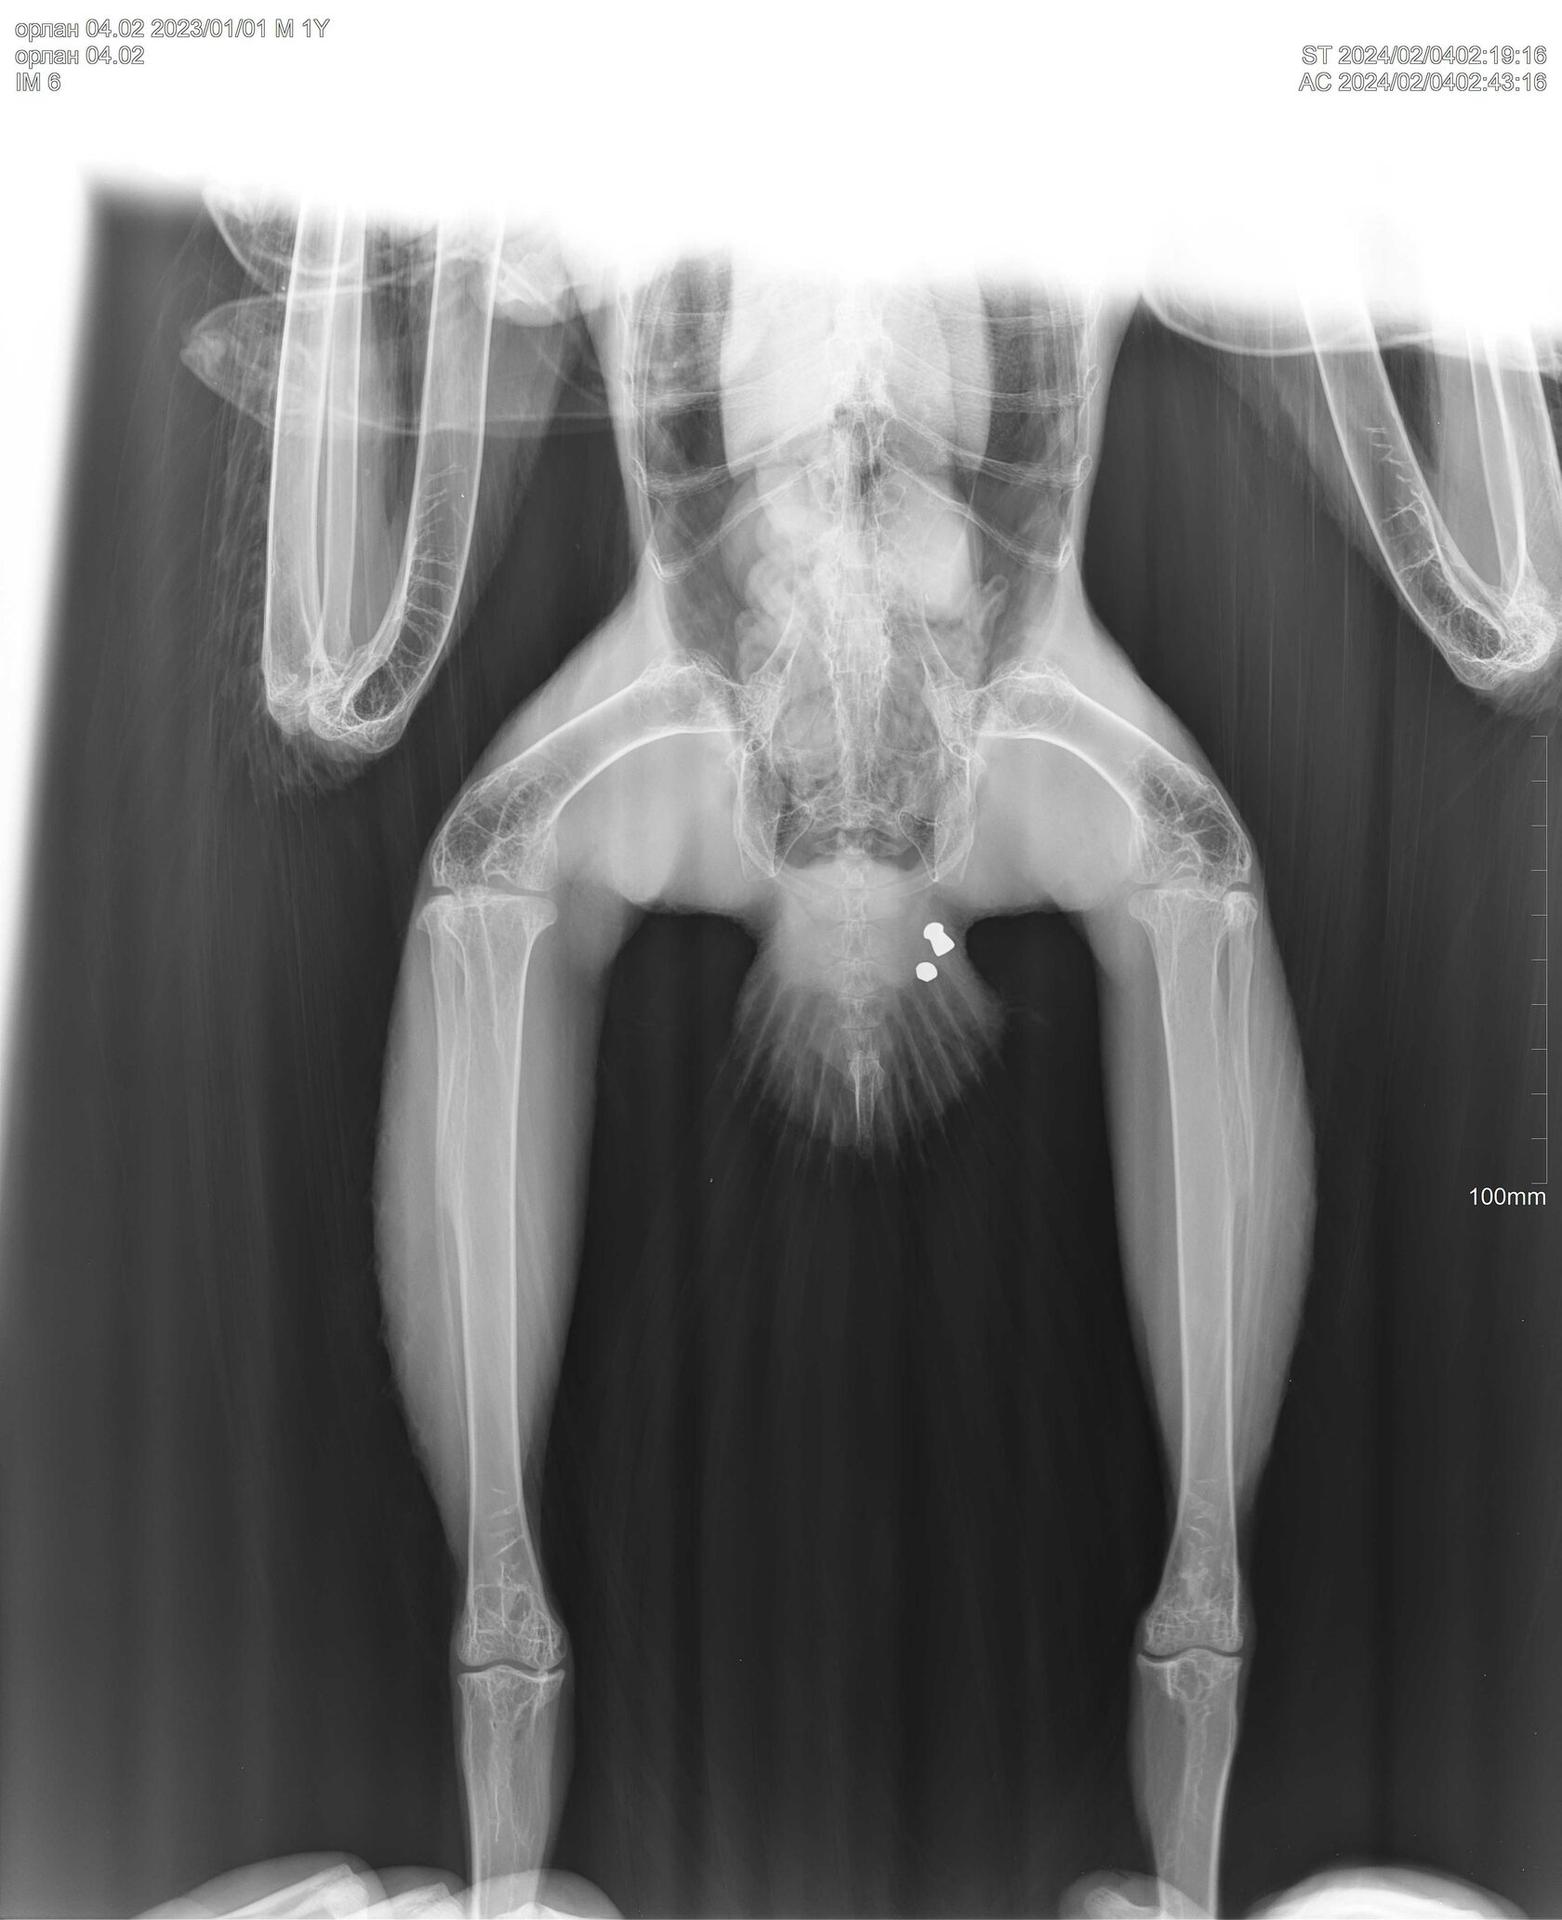

Рентгеновский эффект создает фантастические композиции в этих фотографиях девушки, чье тело становится прозрачным, демонстрируя скелет и внутренние органы. Она позирует в разных позах, ее силуэт светится загадочным свечением. Каждый кадр передает атмосферу научной фантастики и медицинского искусства. Ее кожа кажется полупрозрачной, позволяя увидеть кости и мышцы. Фотографии рассказывают о хрупкости человеческого тела и его внутренней красоте. Девушка то стоит в задумчивости, то делает грациозное движение. Эти иллюстрации вдохновляют на размышления о человеческой анатомии и уязвимости. Каждая картинка - это момент прозрения, когда внешнее уступает место внутреннему. Девушка воплощает образ современной Медузы, сочетающей красоту и загадочность.

Рентген вк7201к